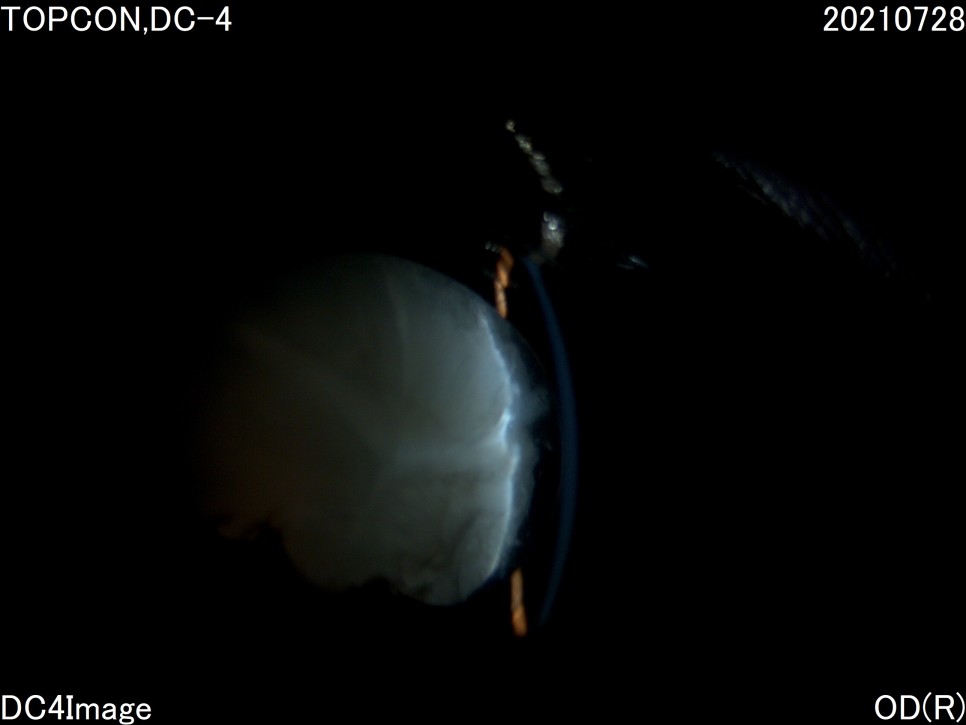

- 초음파 검사

안구 후반이나 전반적인 구조의 이상 유무를 확인하기 위하여 안구 초음파 검사를 실시하였습니다.다행히 파이는 백내장 이외에는 특별한 이상은 없는 것처럼 보였습니다.

수술 후 사진에 보이는 하얀 것은 무엇입니까?위의 사진상, 동공내에 보이는 흰 부분은 「후낭 백탁」이라고 하는 증상과 백내장에 의한 수정체 낭의 섬유화입니다.문자 그대로 백내장 수술 후 수정체의 후낭이라는 부분에 백탁 현상이 생기고, 이는 수정체 전낭 세포의 이주 등에 의해 발생합니다. 완성도는 아이에 따라 다르며, 개의 백내장 수술 후 80%이상에서 볼 수 있습니다.

인간의 경우 레이저로 후낭을 절제하는 시술 등을 하고 있는데, 강아지, 고양이의 경우 이러한 레이저 시술 후 합병증 발생률이 크기 때문에 후낭 백탁으로 인한 시력저하가 심하지 않는 한 별다른 처치를 하지 않고 있습니다.